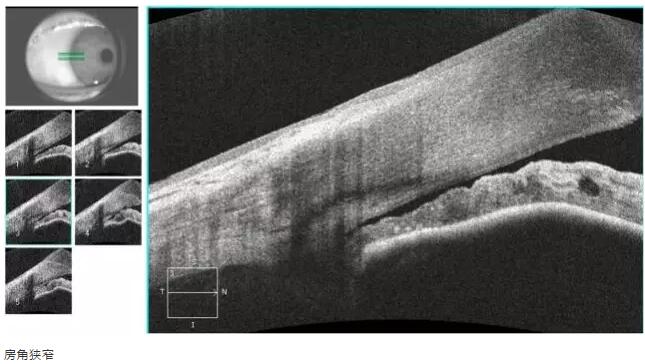

青光眼篇

1:OCT 前节断层扫描可识别出巩膜突、Schwalbe 线 、Schlemm 管 等结构,且辨识度很高,巩膜突(78.9%)、Schwalbe线(93.3%),若对图像进行放大查看, 更佳。